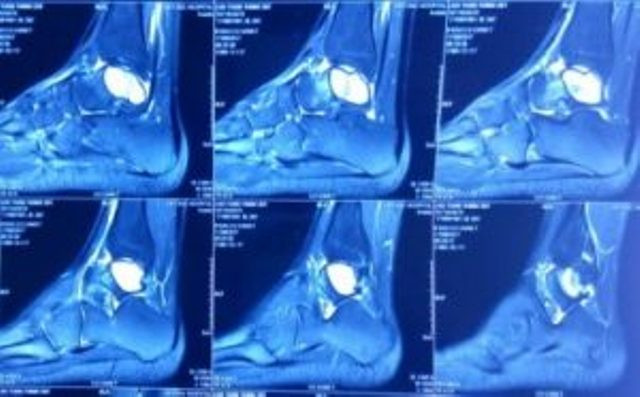

Hình ảnh nang xương phình mạch xương sên trên phim cắt lớp vi tính, cộng hưởng từ.

Bệnh nhân được chỉ định chụp cắt lớp vi tính nhằm đánh giá mức độ phá hủy vỏ xương, kết quả thấy nang xương lớn chiếm toàn bộ thân xương sên, chưa phá hủy vỏ xương. Đồng thời, bệnh nhân được chụp cộng hưởng từ đánh giá tính chất u, kết quả: khối u giảm tỉ trọng trên T1, tăng tỉ trọng trên T2, có vách trong u, hình ảnh mức dịch-dịch.